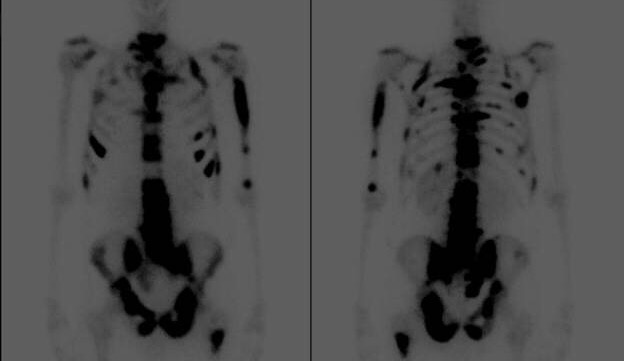

Our dear friend Branden Jensen has terminal end-stage Metastatic Prostate Cancer that has spread thru the majority of his skeletal bones.

After eight months of symptoms, I was diagnosed with aggressive stage 4 metastatic prostate cancer on August 25th, 2013. Tests and a biopsy were scheduled three weeks out. I was admitted to the hospital in Astoria the afternoon of my biopsy and transferred that night to OHSU in full renal failure. There I underwent three surgeries and spent the majority of 11 days in ICU. The medical professionals advised me to transfer home to family and arrangements were made to see an oncologist at Huntsman Cancer Hospital in Salt Lake City. In their care, I had several more surgeries and radiation therapy. By January 2014 my kidneys had healed and the basic treatment I received for advanced prostate cancer began to slow down the progression. My doctor was very open with me and I never expected to live more than a year. I had metastatic disease to the majority of my skeletal bones and pelvic lymph nodes.